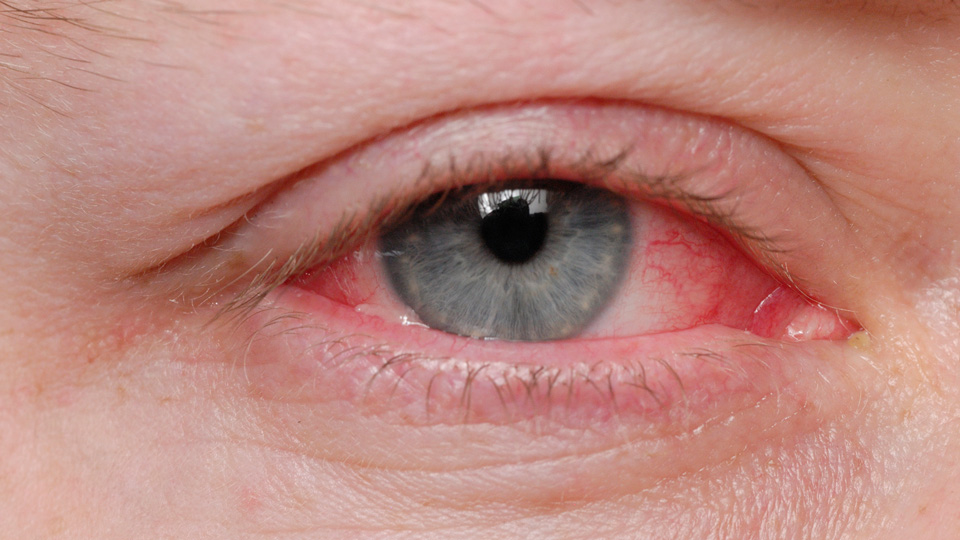

We welcome the Government's consultation aimed at expanding access to medicines for all optometrists and contact lens opticians. Under the new proposals, the sector would be able to provide a wider range of medications to treat minor eye conditions. ow.ly/rwnO50WRiQC

The Department of Health and Social Care has launched a consultation into the extension of medicine responsibilities for optometrists and contact lens opticians. The consultation is now open and practitioners are encouraged to respond. Find out more ➡️ ow.ly/Oy7f50WSiAO